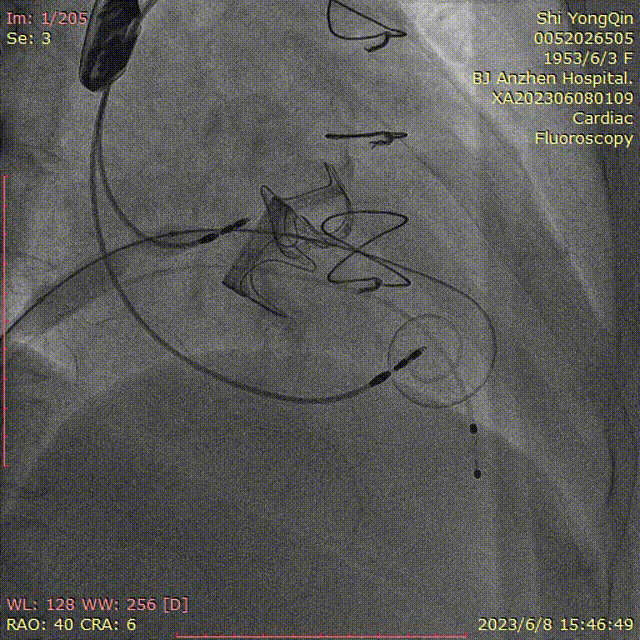

患者全麻,摆体位可寻找衰败生物瓣的切线投照体位,后消毒铺巾,穿刺双侧股静脉,左侧股静脉植入临时起搏器,右侧股静脉作为主入路,在超声指引下,按术前CT评估要求穿刺房间隔到达左心房,肝素化后(ACT>250秒),导入Agilis可调弯鞘管到达左心房,Pig造影导管跨过二尖瓣到达左心室心尖部,导入Safari导丝到达左心室;以12×40mm球囊扩张房间隔确认SAPIEN 3瓣膜可通过后,导入反向安装的23mm+3ml瓣膜到达下腔静脉,组装成功后,翻转其调弯系统后送入到左心房,跨过衰败的二尖瓣,在切线投照体位定位精确后,快速心室起搏下释放瓣膜,见瓣膜位置良好,超声显示无瓣周漏,测量左心室和桡动脉压差稍增高,超声显示LVOT流速稍增快;撤出瓣膜输送系统及导丝,撤出临时起搏电极,局部加压包扎,患者清醒后安返病房。

瓣膜导入

瓣膜的定位及释放